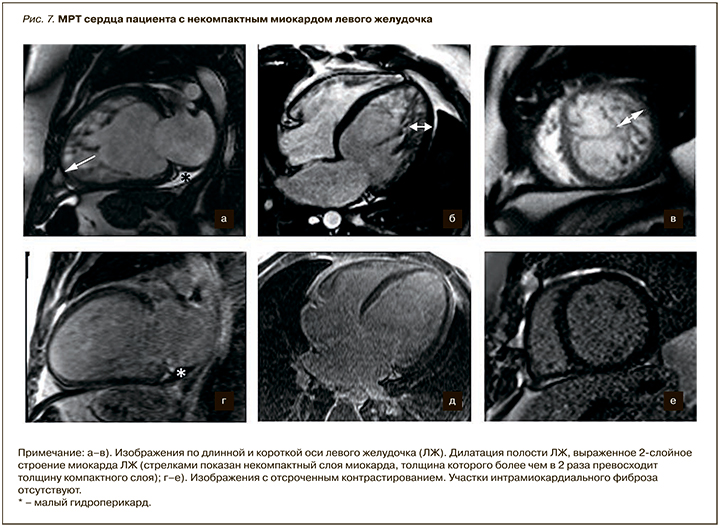

К неклассифицируемым КМП относят синдром некомпактного миокарда и синдром «такотсубо», а также ряд еще более редких болезней сердца. Некомпактный миокард левого желудочка (НМЛЖ) характеризуется чрезмерной трабекулярностью миокарда ЛЖ и образованием глубоких межтрабекулярных пространств. В норме массивные мышечные трабекулы могут встречаться в ПЖ, при этом наличие их в ЛЖ считается патологией. НМЛЖ может сочетаться также с рядом врожденных болезней сердца, нарушениями ритма сердца. ЭхоКГ, МРТ и МСКТ являются основными методами диагностики НМЛЖ. Предложены следующие диагностические критерии НМЛЖ: отсутствие сопутствующей патологии сердца, приводящей к изменению структуры миокарда; выявление двухслойной структуры утолщенной стенки левого желудочка – компактного эпикардиального и некомпактного эндокардиального слоев, причем соотношение между ними превышает 1:2, 3 [25]. Специфичность диагностики НМЛЖ повышает применение критерия массы миокарда [26]. При этом масса некомпактного миокарда должная составлять более 20% от массы компактного миокарда ЛЖ. На рисунке 7 представлены Р-изображения пациента с некомпактным миокардом ЛЖ.

Наиболее часто бывает вовлечена верхушка ЛЖ, миокард боковой и нижней стенок ЛЖ. Данные по результатам исследования с контрастированием противоречивы и варьируют от полного отсутствия участков отсроченного накопления контрастного препарата до наличия очагов субэндокардиального, интрамурального и трансмурального контрастирования.